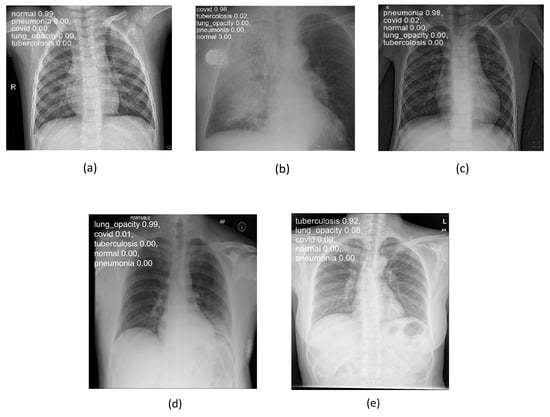

Figure 8 shows some examples of lung images, each corresponding to its respective pathology, with the classification percentage result for all classes. As can be observed, the model performs very well even on images it has never seen before, achieving a rate of accuracy ranging from 92 to 99%.

Figure 8. Lung disease classification for (a) “normal”, (b) “covid”, (c) “pneumonia”, (d) “lung_opacity”, and (e) “tuberculosis” classes using testing set.